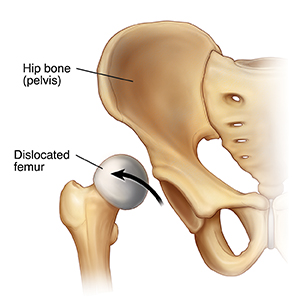

Developmental hip dysplasia happens when the rounded top of the leg bone (the femoral head) slips partly or completely out of the hip socket. The hip socket may be too small or too shallow. This problem is more common in female children, in firstborn children, and in children born into families with a history of this condition. It is also more common in babies who are positioned feet first (breech) in the uterus.